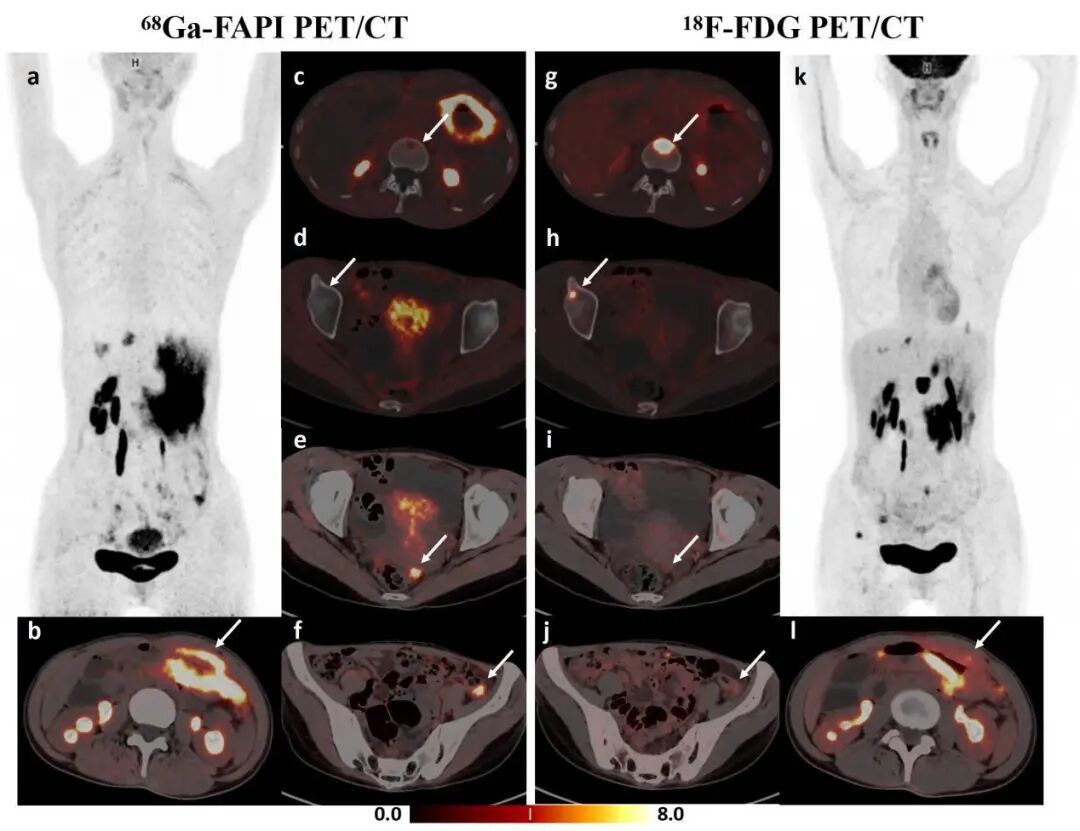

图2 68Ga-FAPI PET/CT(左图)清晰显影了隐匿的腹膜转移灶;18F-FDG PET/CT(右图)有效检出隐匿的骨转移灶;双探针优势互补,协同提升分期准确性

2. 显著提升术前腹膜转移检出率与胃癌分期准确率:腹膜转移是晚期胃癌的主要转移途径之一与复发根源,严重制约患者预后。传统影像学检查(如CT、18F-FDG PET/CT等)对早期、微小的腹膜转移灶极易漏诊,导致临床分期低估,从而影响精准治疗策略的制定。前期,团队研究成果显示,68Ga-FAPI PET/CT对腹膜转移的检出灵敏度高达91.7%,是传统18F-FDG PET/CT的两倍以上。这项技术如同鉴别腹膜转移时点亮“高清探灯”,显著照亮了既往的诊断盲区。此外,团队联合应用68Ga-FAPI 与18F-FDG双探针PET/CT,使远处转移灶检出的灵敏度提升至97.1%,为胃癌分期提供重要的分子影像学依据。